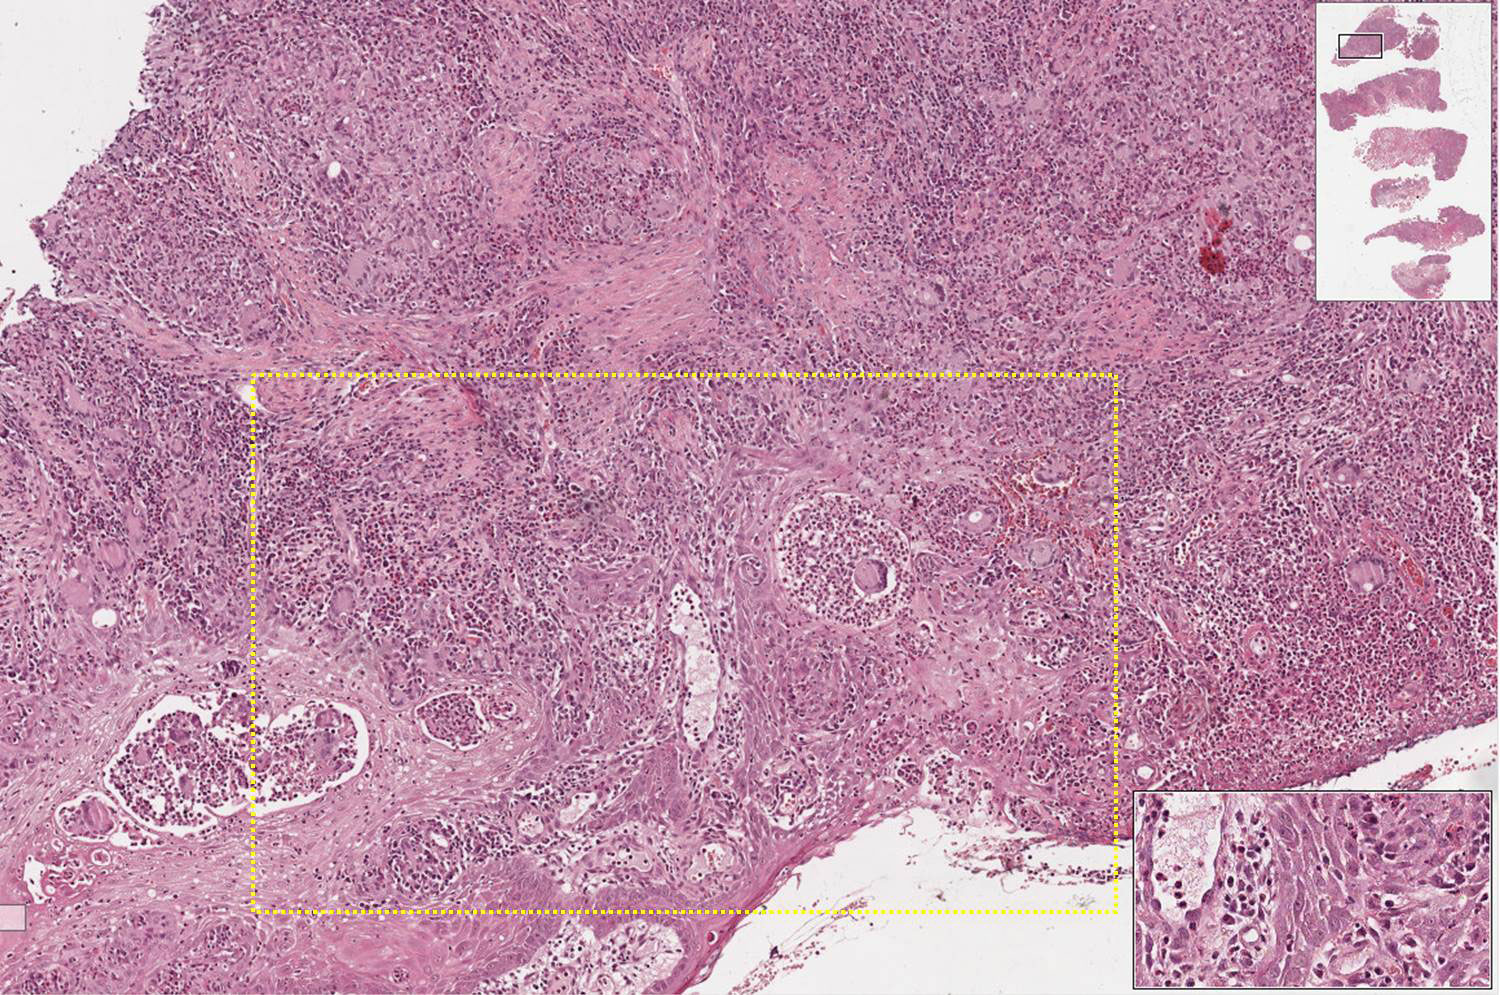

Os aspectos morfológicos observados (granulomas no tecido conjuntivo, hiperplasia pseudoepiteliomatosa e microabscessos no tecido epitelial) são os mesmos. Essa técnica pe utilizada para evidenciar o Paracoccidioides brasilienses, agente etiológico da paracoccidioidomicose, e confirmar o diagnóstico. Em lâminas coradas por HE nem sempre é possível evidenciar o espaço claro na célula gigante, o qual costuma sugerir presença deste microrganismo.